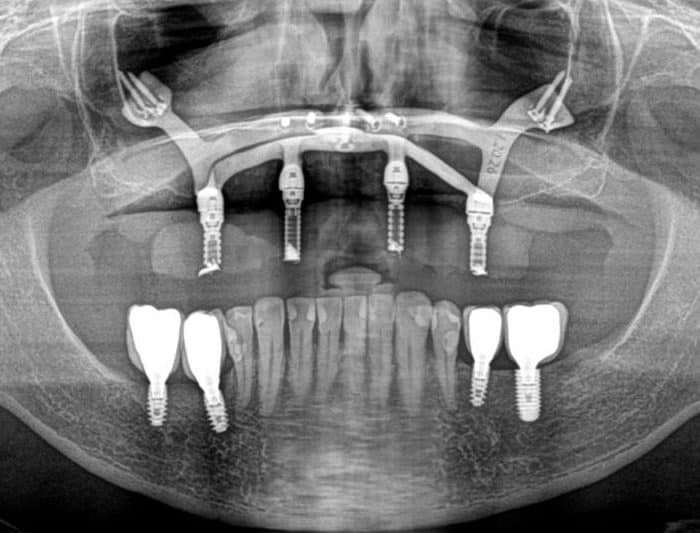

Design My Implants uses CT scans to create tailored bone reconstruction systems. Our titanium parts are finely polished and treated for optimal bone bonding. We strategically place the device and screws for maximum durability. The screws are set in the densest bone areas for secure fixation. Our entire process emphasizes precision for lasting results.

Rigorously Validated Design

Each design undergoes structural analysis using finite element methods, confirming the implant’s ability to withstand the various forces it will encounter in the mouth.